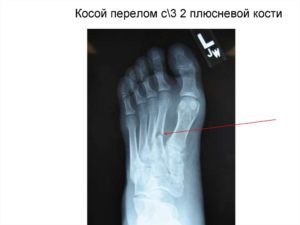

Перелом второй плюсневой кости: последствия

В медицинской практике изолированный перелом второй плюсневой кости встречается крайне редко. Механизмы получения переломов костей плюсны и особенности строения стопы человека (наличие высокого свода) предопределяют, что вторая кость ломается или вместе с соседними, или при повреждении всех плюсневых костей одновременно.

Фото, рисунки, рентгеновские снимки и видео в этой статье помогут лучше разобраться в особенностях повреждения и существующих сегодня схемах лечения.

В классификации, опирающейся на анатомические принципы, перелом второй плюсневой кости 90% попадает в класс Б – переломы диафиза (костного тела), и только 10 % в класс А – изломы шейки.